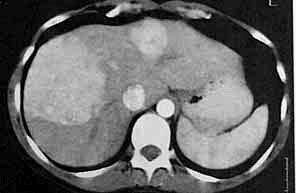

5个月后复查显示两个病灶没有变化.

(病例经腹腔镜证实为肝局灶结节增生)